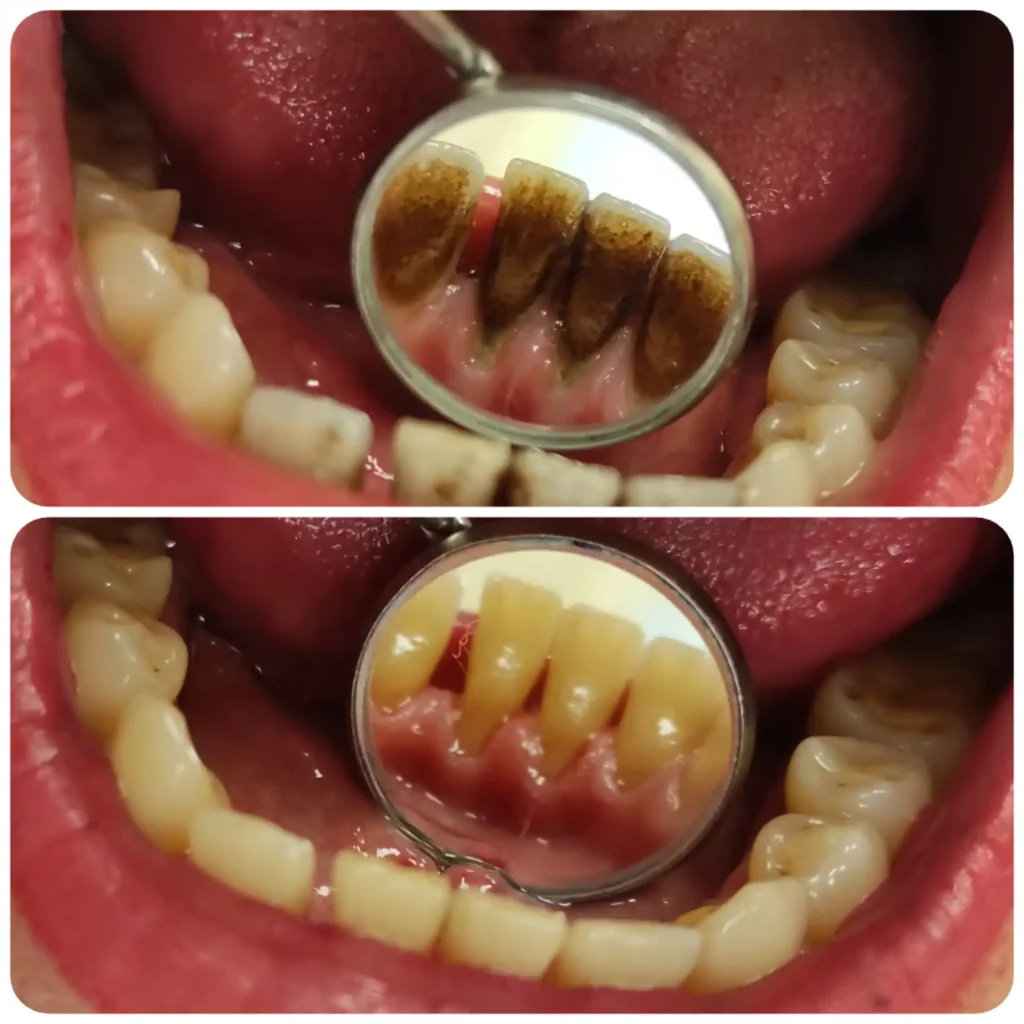

Fő érdeklődési területeim közé tartoznak az esztétikai beavatkozások, tömések, könnyebb gyökérkezelések, hagyományos fogpótlások készítése, kivitelezése. Fontosnak tartom a fogak megfelelő rehabilitációját és szájban tartását. Tudásomat hazai és külföldi szakmai továbbképzésekkel folyamatosan fejlesztem.